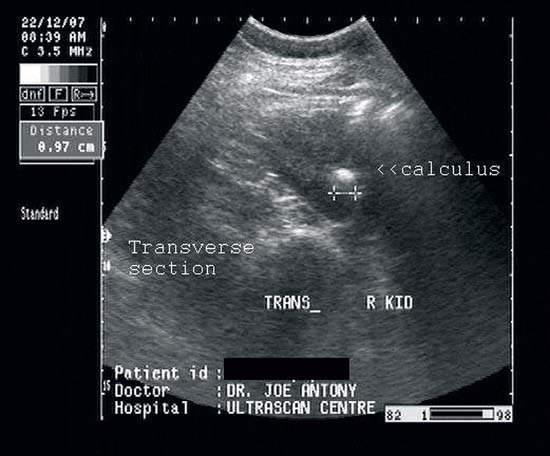

При ультразвуковом исследовании почек можно увидеть камни, оценить их размеры, местоположение и изменения в стенках мочевыводящих путей, вызванные их присутствием. Этот метод является ключевым для диагностики мочекаменной болезни.